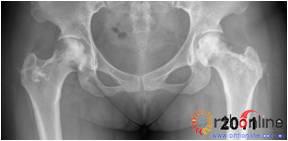

2.2 影像学结果 影像学结果与临床结果基本同步。临床结果优的36髋,34髋维持圆形且修复较完全(图1)。1例双髋Ⅲa激素性(SARS患者)ONFH,术后随访7年8月,X线片显示股骨头虽不圆,但临床HHS评分90分为优(图2)。功能为良的12髋,7髋股骨头不圆,但股骨头与髋臼匹配好,其余5髋股骨头维持圆形。临床评定为差的17髋,股骨头均有超过4mm塌陷,股骨头与髋臼匹配不好,股骨头内无折断,MRI未显示骨髓水肿,关节间隙呈不对称改变,CT扫描示软骨下骨折,MRI显示骨髓水肿。

图2 男,22岁,激素性骨坏死,(1)双侧股骨头骨髓水肿,ARCO分期Ⅲa期,C3型;(2)X线片示股骨头塌陷,术前关节功能差(Harris评分50分);(3)打压植骨术(未加BMP2)后7年,关节功能好(Harris评分90分),股骨头有轻度塌陷,但头臼匹配好;(4)蛙式位显示股骨头臼匹配好